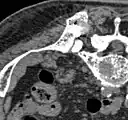

Scanner d'une métastase ostéocondensante dans l'os du crâne d'un patient souffrant d'un carcinome de la prostate. On reconnaît clairement l'extension de la métastase au-delà des limites initiales de l’os.

Par comparaison, scanner de métastases ostéolytiques dans l'os du crâne d'une patiente souffrant d'un cancer du sein. On distingue une ostéolyse plus grande sur le front, et plusieurs plus petites.